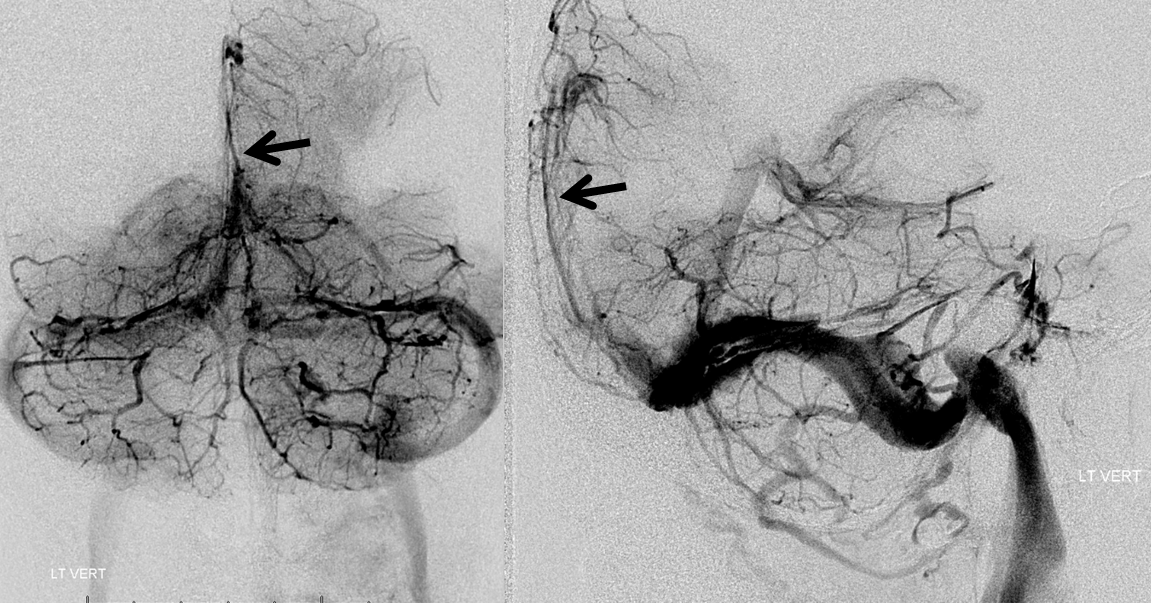

Below is a case of severe venous sinus thrombosis and secondary parenchymal venous infarcts

The explanation for the above tragic pattern is below. On the right, sigmoid and transverse sinuses are patent. However, the Labbe is hypoplastic, and majority of outflow used to go to the Trolard, into the now occluded SSS. There is no other effective way to go — the trolard tries to decompress via a left diploic vein, and convexity tries to access the deep venous system (which normally should not be well-seen in setting of hypoplastic right A1 segment). The left situation is much better, as well-developed superficial sylvian veins drain into the patent Cavernous Sinus. Thus, despite thrombosis of the left transverse and sigmoid sinuses, the left hemisphere is doing better, while the right one, which has patent transverse and sigmoid sinuses, is devastated.

Post venous thrombectomy — with limited results. Note presence of same left diploic vein as seen in right ICA injection, and connection between the distal superior sagittal sinus and the deep venous system via the inferior sagittal sinus.

Sagittal Sinus Thrombosis — collaterals.

All of the above anatomic knowledge can become very useful in evaluation of venous thrombosis. Numerous collateral pathways develop in this setting attempting to compensate for the loss. The most dramatic cases usually involve the largest channel — the superior sagittal sinus. In this case, a man presented with what initially was thought to be vasculitis-related brain hemorrhage. Subsequent workup led to an angiogram, where sagittal sinus thrombosis with extensive trans-cerebral and trans-osseous emissary vein collateral channels was seen. In retrospect, these findings were present on the patient’s earlier contrast MRI. “Venovibe” or other contrast-enhanced MR venograms can very sensitive, particularly when interpreted with the appropriate index of suspicion. Noncontrast 2-D time of flight MRV I consider to be next to useless as a problem-solving technique. Any thin-slice postcontrast T1 study is vastly superior.